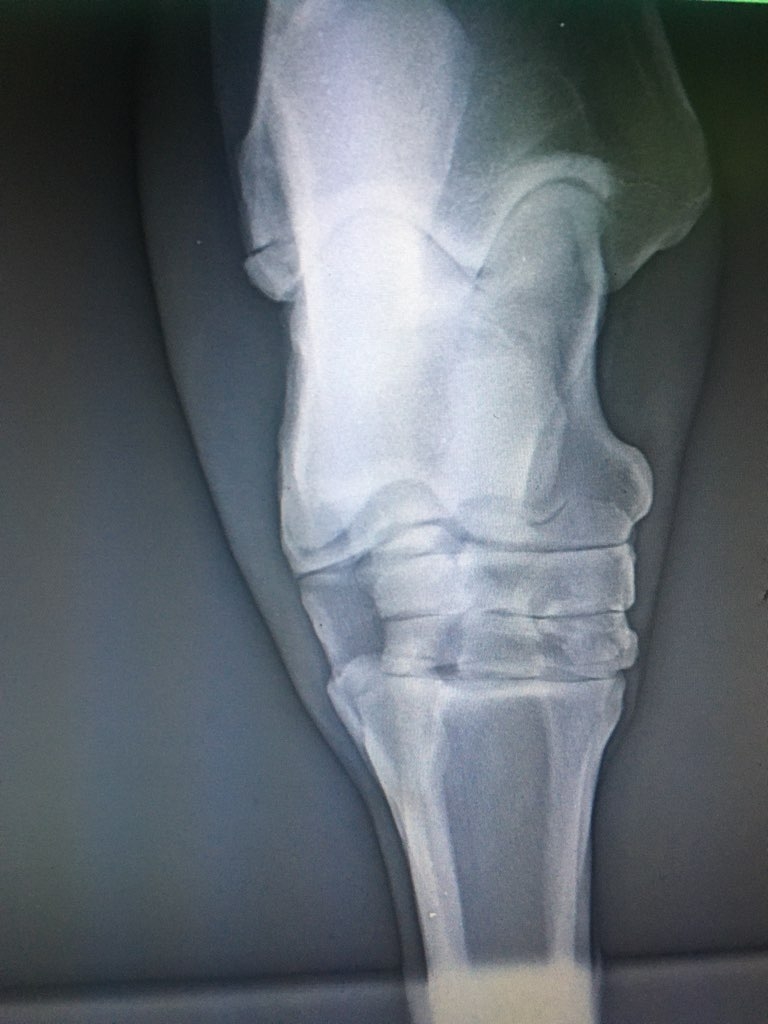

| Dire merci | Bonsoir à tous, Je ne poste pas pour moi mais pour une amie dont le cheval a lourdement chuté au pré et s'est fait une fracture de la malléole à chaque postérieur... Plusieurs vétérinaires ont vu le cas, le cheval est debout, marche trotte parfois mais a quand même mal évidemment... Quelqu'un a déjà eu le cas ? Quel suivi a été mis en place ? Opération ? Convalescence ? Si convalescence quel protocole ? Car les avis divergent sur la gestion du cas. J'ai les radios que je mets en spolier. Merci à tous ![]() Clichés : |

| Dire merci | La vache il s'est claqué les jambes en tombant comme un sac sur le côté ?! ![]() Dans l'immédiat, c'est ni comminutif, ni intra articulaire, ni déplacé, et sur une faible surface. Donc " Positif" Jamais eu le cas . Je dirais immobilisation stricte au box si le cheval tient le box durant quelques semaines (4 a 6) puis radio de contrôle et petit paddock avec des protections type trotteur avec un bon bilan loco a la clef. Et vu le placement et le risque ligamentaire, attention au sol et au parage si le cheval reprend le boulot. Mais encore une fois, jamais eu le cas donc... |